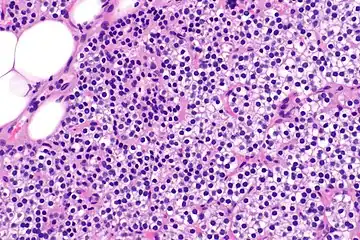

Parathyroid hyperplasia high mag.

Parathyroid glands are normally composed of chief cells, adipocytes and scattered oxyphil cells.[27][14] Chief cells are thought to be responsible for the production, storage and secretion of parathyroid hormone. These cells appear light and dark with a prominent Golgi body and endoplasmic reticulum. In electron micrographs, secretory vesicles can be seen in and around the Golgi and at the cell membrane. These cells also contain prominent cytoplasmic adipose.[27][14] Upon onset of hyperplasia these cells are described as having a nodular pattern with enlargement of protein synthesis machinery such as the endoplasmic reticulum and Golgi. Increased secretory vesicles are seen and decreased intercellular fat is characteristic.[27][24] Oxyphil cells also appear hyperplasic however, these cells are much less prominent.

Biochemically, there are changes in function between normal and nodular hyperplastic parathyroid glands. These changes involve proto-oncogene expression and activation of proliferative pathways while inactivating apoptotic pathways.[28] In nodular parathyroid tissue increased expression of TGF-a, a growth factor, and EGFR, its receptor, results in aggressive proliferation and further downregulation of vitamin D receptors, which act to suppress hormone secretions.[25][8][28] Furthermore, the proliferative marker, Ki67 is seen to be highly expressed in the secondary nodular hyperplastic state.[28][25] Tumour suppressor genes have also been highlighted as being silenced or degraded in nodular hyperplastic parathyroid tissue.[8][28] One such gene, p53, has been shown to regulate multiple tumour suppressor pathways and in tumorigenesis can be degraded by b-catenin. This pathway, in some aspect, is mediated by CACYBP, which is highly expressed in nodular parathyroid hyperplasia.[28]